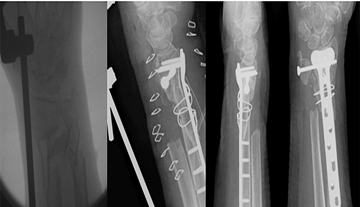

Examples of applications of bone grafts are illustrated in Figures 1-3.

Figure 1: Metaphyseal comminution with a large segment of bone loss.

K wires did not adequately hold the temporary reduction of the fracture. A synthetic bone graft was used to fill the bone void and maintain the stability of reduction for fixation. (Lt: intra-op fluoro showing metaphyseal defect; Middle: immediate post-op; Rt: four months).

Figure 2: Large metaphyseal defect bridged with a corticocancellous autologous iliac crest graft shows union at 3-months.

Lt to Rt: intra-op fluoro showing metaphyseal defect, immediate post-op, AP + Lat at three months.

Figure 3: Metaphyseal bicortical defect with fracture shortening.

Bone graft in the form of a bone block was used to restore the radial height and stabilization of the fracture reduction before the application of the locking plate.